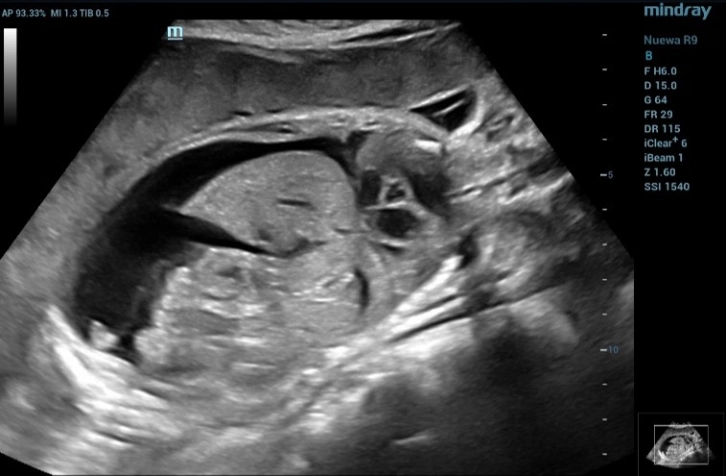

4. Abdominal anomalies (Hydrops fetalis)

In Figure 8, there is significant fluid accumulation observed around the fetus in both the abdominal cavity (ascites) and thorax (pleural effusion).

In Figure 9 reveals hepatomegaly as a consequence of extramedullary hematopoiesis in response to anemia.

fluid collection around the fetus

Figure 8 Shows fluid collection around the fetus